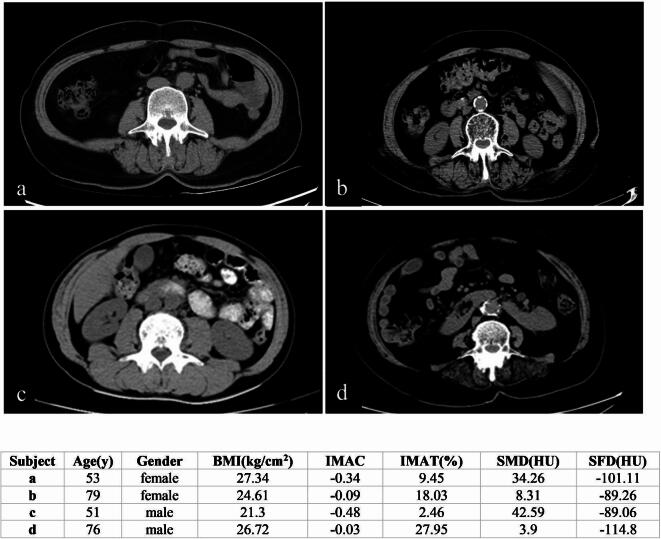

本研究旨在确定肌间脂肪组织(IMAT)或肌内脂肪组织含量(IMAC)对骨骼肌密度(SMD)的影响更大,并探讨其潜在机制。我们招募了292名没有肌肉骨骼系统疾病的住院患者,他们都接受了腹部CT检查。肌肉参数包括骨骼肌面积(SMA)、骨骼肌指数(SMI)、SMD、IMAC和IMAT,以及脂肪参数-腹壁皮下脂肪面积(SFA)和皮下脂肪密度(SFD)由两名肌肉骨骼放射科医生在第三腰椎(L3)水平使用ImageJ软件测量。单因素方差分析采用LSD(组间比较采用卡方检验,p < 0.05)或Dunnett's T3检验(p < 0.05)。研究结果显示,年龄、IMAT和IMAC影响SMD,其中IMAT的影响最为显著。

This study aimed to determine whether intermuscular adipose tissue (IMAT) or intramuscular adipose tissue content (IMAC) has a greater effect on skeletal muscle density (SMD) and to explore the underlying mechanisms. We recruited 292 inpatients without musculoskeletal system disease, all of whom underwent abdominal CT. Muscle parameters, including skeletal muscle area (SMA), skeletal muscle index (SMI), SMD, IMAC, and IMAT, as well as fat parameters-subcutaneous fat area (SFA) and subcutaneous fat density (SFD) in the abdominal wall-were measured by two musculoskeletal radiologists using ImageJ software at the third lumbar vertebra (L3) level. One-way ANOVA with LSD (chi-square test for group comparisons where p > 0.05) or Dunnett's T3 test (p < 0.05) was employed to compare muscle parameters between genders and across age groups. The relationship between SMD and muscle measurements was analyzed using Spearman's correlation coefficient. Multiple regression analysis identified and compared factors influencing SMD. SMD was highly correlated with IMAT and IMAC (p < 0.05), moderately correlated with gender, age, and SFA (p < 0.05). Multiple linear regression analysis indicated that IMAC, IMAT, and age significantly affected SMD (p < 0.05), with the order of influence being IMAT (β = -0.616), IMAC (β = -0.429), and age (β = -0.098). SFA and gender did not significantly affect SMD (p > 0.05). The findings revealed that age, IMAT, and IMAC influence SMD, with IMAT exerting the most significant impact.